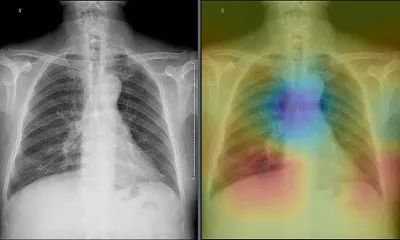

此次推出的10款智能诊断应用,均针对不同的医疗场景和当下亟需解决的医疗痛点。以“智能体检读片”为例,在中国,一家体检中心每天会产生上千例X光胸片,但平均往往只有几十例存在异常,医生要将大量时间精力耗费在逐一阅读健康胸片上。这样不仅医生负担重,患者看病也要耗费更多等待时间。现在,只需在X光设备上安装这款“智能体检读片”智能诊断应用,就能有效解决这一痛点。它如同一位医生的“AI助理”,可快速从海量影像中预筛出健康的X光胸片,只将有疑似疾病的提交医生阅读。

一键自动标注疑似病灶

据联影智能核心团队成员之一郑介志介绍,为了保证这位“AI助理”筛选胸片的精准程度,团队使用了20万个X光胸片数据对其进行深度学习训练。目前,在肺结节、肺水肿、胸膜增厚等14种肺部疾病中,这位“AI助理”已有9种诊断精准度排名世界第一,超过美国国立卫生院、美国斯坦福大学相关研发团队。